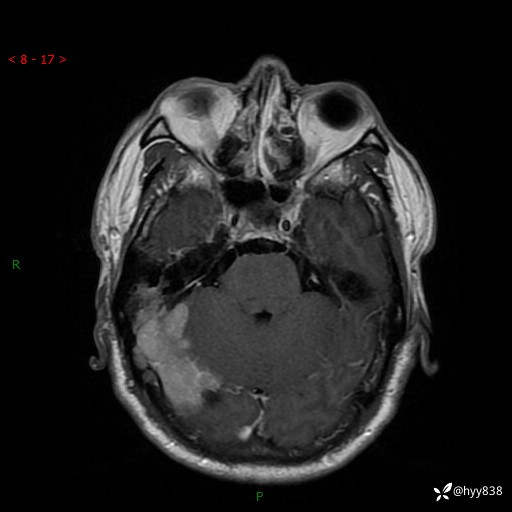

患者性别:男

患者年龄:56岁

简要病史:外院CT提示脑膜瘤,为进一步诊治来我院

辅助检查:MRI

临床诊断:颅脑占位

颅脑MRI平扫+增强